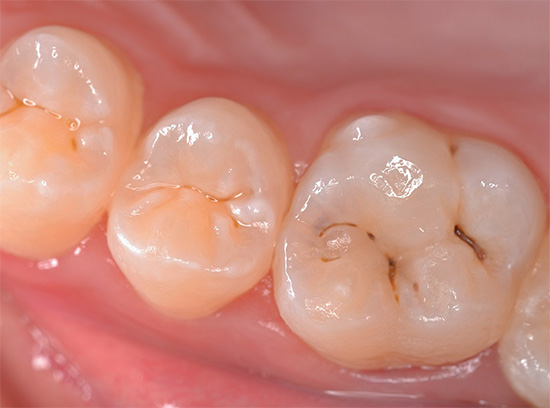

Ad esempio, di seguito nella foto - carie delle fessure. Sui denti, appare sulla superficie masticatoria nelle depressioni naturali chiamate ragadi. In alcuni casi, le linee nere sono così piccole che la sonda dentale e lo sguardo del medico non indugiano su di esse, ma spesso il problema è chiaramente visibile ad occhio nudo:

La carie da fessura è pericolosa perché vaste aree della dentina colpita possono essere nascoste sotto danni allo smalto apparentemente minori. Per una migliore comprensione, guarda un video che mostra schematicamente come la carie penetra nei tessuti dei denti profondi:

E poi nella foto: la cavità orale con i denti colpiti dalla carie delle fessure. Linee scure visibili, sebbene non grandi, ma chiaramente visibili sui molari. L'installazione di otturazioni qui non può più essere evitata, ma è del tutto possibile prevenire lo sviluppo della pulpite.